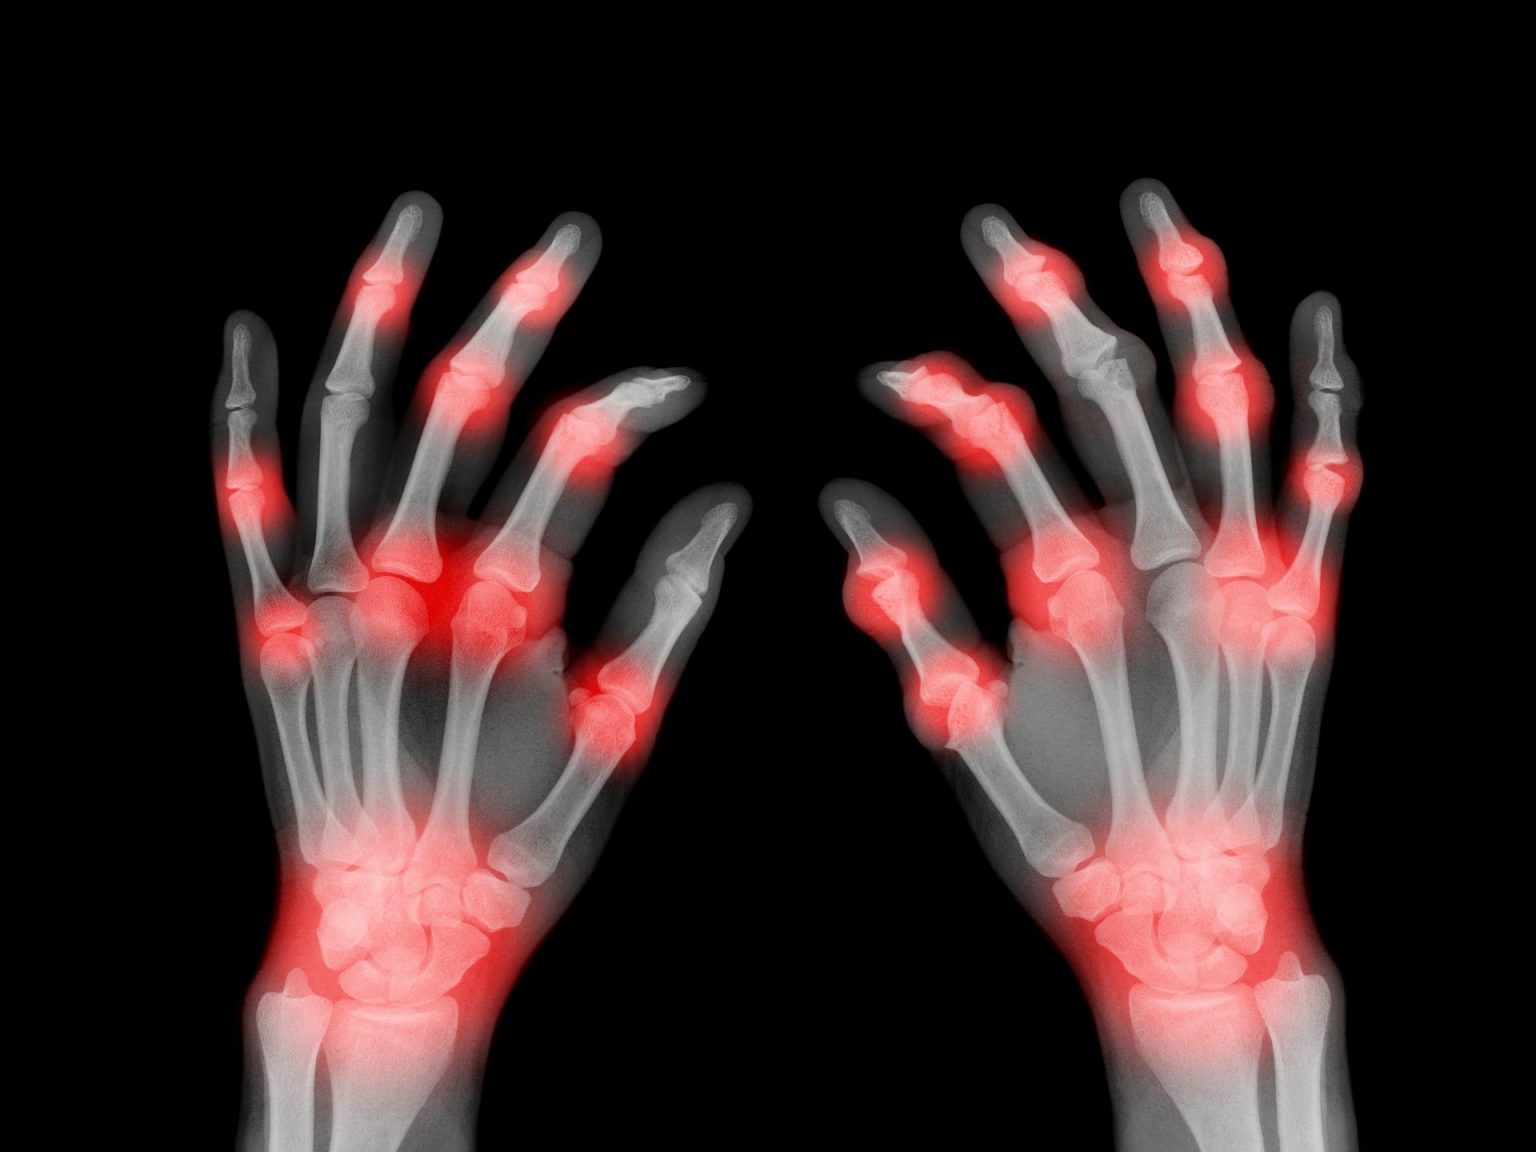

وأوضحت الجمعية أن أعراض متلازمة الألم الناحي المركب تتمثل في آلام شديدة غالبا ما تبدأ في الذراعين واليدين والقدمين، وفي كثير من الأحيان يمكن أن تتفاقم الحالة مع مرور الوقت، فينتشر الألم إلى باقي أنحاء الجسم؛ مثل: الأعصاب والعظام والعضلات.

وتشمل الأعراض -أيضا- احمرارا وتورما وسخونة الطرف المصاب، وتراجع القدرة على تحريكه، بالإضافة إلى الخدر والوخز والحساسية للمس.